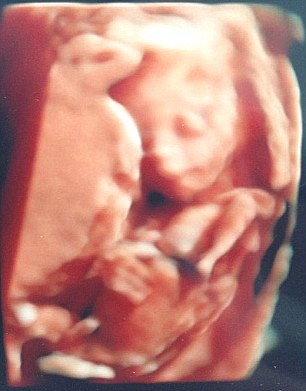

報道稱,住在默西賽德郡布特爾的西沃恩·鮑威爾(Siobhan Powell)在懷孕期間一心想趕快見到女兒的樣子,在腹中胎兒20周大時照了超聲波。當掃描出來后,鮑威爾大吃一驚,腹中的女兒竟然抱著一只“貓鼬”。

超聲波圖像是顯示,女嬰的頭輕輕靠著一只“貓鼬”。“貓鼬”的眼睛、耳朵、爪子和尾巴都清晰可見。就連給鮑威爾照超聲波的醫(yī)生都直呼她肚子里“有貓鼬”,不過醫(yī)生解釋稱,這只“貓鼬”其實是子官內的組織。

如今,鮑威爾的女兒已經半歲大,一個貓鼬造型的毛絨玩具成了小姑娘出生以后的第一個玩具。鮑威爾表示,女兒非常喜歡貓鼬玩具,都舍不得放手,她打算等女兒長大以后,把“貓鼬玩具”的超聲波照片拿給她看。